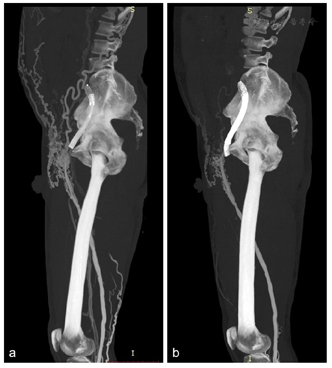

双下肢静脉CTV像示左侧髂外静脉-髂总静脉-下腔静脉支架留置影,左侧髂外静脉远端可见少许对比剂充盈,余支架管腔内可见低密度充盈缺损影,左侧髂外静脉、髂总静脉未见对比剂充盈;左侧腹股沟可见多发侧支血管显影,左侧腹壁内侧-左肾静脉侧支血管建立影像(图1,图2),右侧髂外静脉、髂总静脉及下腔静脉可见对比剂充盈,密度不均匀;双足、双下肢皮下多发迂曲静脉显影,双侧大隐静脉充盈良好,左侧股静脉近端充盈缺损,血管纤细,密度不均(图1)。诊断:左侧髂外静脉-髂总静脉-下腔静脉支架留置,支架内血栓形成,左侧腹股沟区、左侧腹壁内测-左肾静脉及腹壁静脉建立。介入治疗后复查双下肢静脉CTV,可见左侧大隐静脉开口以近支架内血管大致通畅,支架以远端下肢静脉未见明确显影,左侧腹股沟区侧支循环较前减少,左侧腹壁内侧-左肾静脉侧支血管较前减轻(图3、图4)。

下肢静脉栓塞的诊断金标准为DSA检查[1],但DSA是有创检查,准备时间长,耗费人力物力,同时DSA存在过量辐射暴露风险且检查费用较高,检查过程中易损伤血管壁导致新鲜血栓形成[2,3,4]。对比DSA,CT血管检查操作简便,显影效果好,安全微创,对比剂用量少,成像范围大,辐射剂量低。根据对比研究,可以准确评估下肢静脉的通畅性,能展现整个下肢静脉系统情况及静脉栓塞疗效评估,与DSA吻合度高。双源CT低kV高mAs球管技术,在降低患者辐射剂量前提下,增强了碘对比剂衰减,在CT血管检查中用低流速低对比剂用量亦可获得高质量的CT血管诊断图像。本例双下肢CTV采用90kV,双筒双流速度2.5ml/s直接注入下肢静脉各100ml混合剂(造影剂10%+盐水90%),可获得可观的静脉血管图像(图1)。对比常规CT(120kV),低kV技术大幅度降低辐射剂量。此外,CT血管后处理灵活方便,结合探针分析,更是可以细节、清晰地观察支架内外管腔及管壁情况(图2、图3),为临床诊断提供准确的影像学资料,为患者病变及时发现及进一步治疗提供可靠依据[5]。CT作为微创检查方式,"三低"双下肢CTV可常规应用,替代传统120kV,满足临床诊断需求同时提高患者的舒适度,降低辐射剂量,减少并发症,并适合血栓患者术前明确诊断及术后疗效评估(图4)。为了实现常规低kV血管成像,其他先进的技术也被使用,如CARE Dose4D(实时自动曝光控制)和ADMIRE(高级模型迭代重建)。在本病例中,有效剂量仅为0.65mSv。